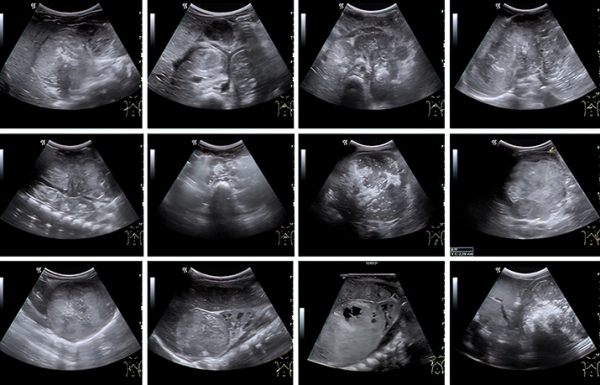

Во время УЗИ на амбулаторном этапе забрюшинная опухоль, как правило, определяется по достижении так называемого диагностического объема в несколько кубических сантиметров. При этом врач уверенно может установить факт наличия образования, его эхоструктуру, чего уже достаточно для направления ребенка на дообследование (см. рис 2).

Рисунок 2. Сонографические варианты нейробластомы.

Наибольшие трудности специалист УЗД испытывает при установлении органной принадлежности опухоли, когда она уже достигла больших размеров. К примеру, медиана диагностического объема впервые установленной нейробластомы у младенца составляет 75 (26–208) см3, а для опухоли почки и того больше — 317 (226–524) см3. Именно эти новообразования приходится дифференцировать, в том числе и в онкологическом центре, т. к. химиотерапевтическое лечение опухоли Вильмса в ряде случаев начинают по результатам диагностики на основе визуализирующих методов исследования.